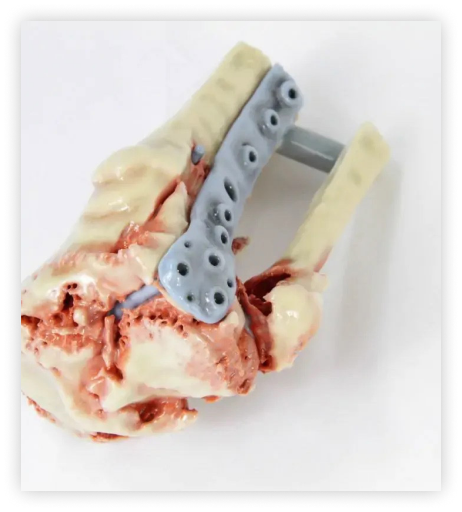

Asthi - Bone-Like 3D Printed Training Models

Our bone-like training models are made from a durable, bone-like material that closely mimics the texture and feel of real bone. These models are perfect for practising surgical techniques and procedures, as they provide a realistic simulation of human bone. Making it easier for medical professionals to study and understand human anatomy. Our models are available in various sizes and can be customised to meet your specific needs.

Asthi- Patient-specific 3D printed bone models

3D-printed bone models made of human bone-like material are accurate and highly detailed, providing a realistic representation of the patient’s bone structure. Our models are ideal for surgical training and planning, allowing medical professionals to practice and perfect their skills before performing surgeries on real patients. as they provide a realistic simulation of human bone. Making it easier for medical professionals to study and understand human anatomy”.

oral and maxillofacial

Orthopedics